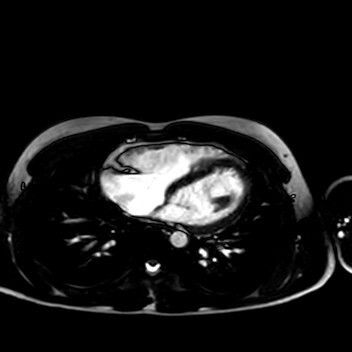

HerzMed2

Abbildung 2: Das kardiale MRT zeigt eine Dilatation und regionale Auswölbung des rechten Ventrikels, reduzierte RV-Ejektionsfraktion, fettige Infiltration des Ventrikelseptums sowie subepikardiale späte Gadolinium-Anreicherung im linken Ventrikel.